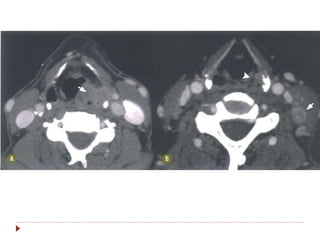

 Massa sólida em tonsilas

palatinas e linguais.

 Massas exofíticas com

realce pós-contraste na

fase venosa, na TC e na

RM.

 Principal diagnóstico

diferencial é com

hiperplaisia linfoide.

 Linfonosos necróticos

podem ajudar no

diagnóstico, sugerindo

neoplasia.